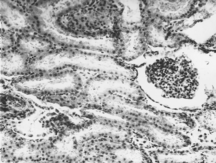

Паренхима почек состоит из четко выраженного периферического коркового вещества и внутреннего мозгового (Рис. 2 ). В состав коркового вещества входят имеющие характерные структуру почечные тельца, состоящие из клубочков капилляров, капсулы клубочка и извитых канальцев (проксимальных и дистальных), а в состав мозгового – прямые канальцы. Проксимальные канальцы имеют диаметр около 60 мкм, полость его варьирует от узкой щели до широкого округлого просвета. Эпителий проксимальных канальцев состоит из одного ряда кубических клеток с равномерно окрашенной цитоплазмой. Ядра округлой формы с четко выраженной хроматиновой структурой. Дистальные канальцы имеют диаметр 35 мкм, выстланы кубическим эпителием, просвет округлый, хорошо выражен.

Собирательные трубочки мозгового слоя выстланы кубическим или призматическим эпителием. Клетки светлые, границы клеток четко выражены.

Рисунок 2. Почки. Группа № 1 (контроль). Паренхима органа состоит из четко выраженного периферического коркового вещества и мозгового слоя. (Увел.400).